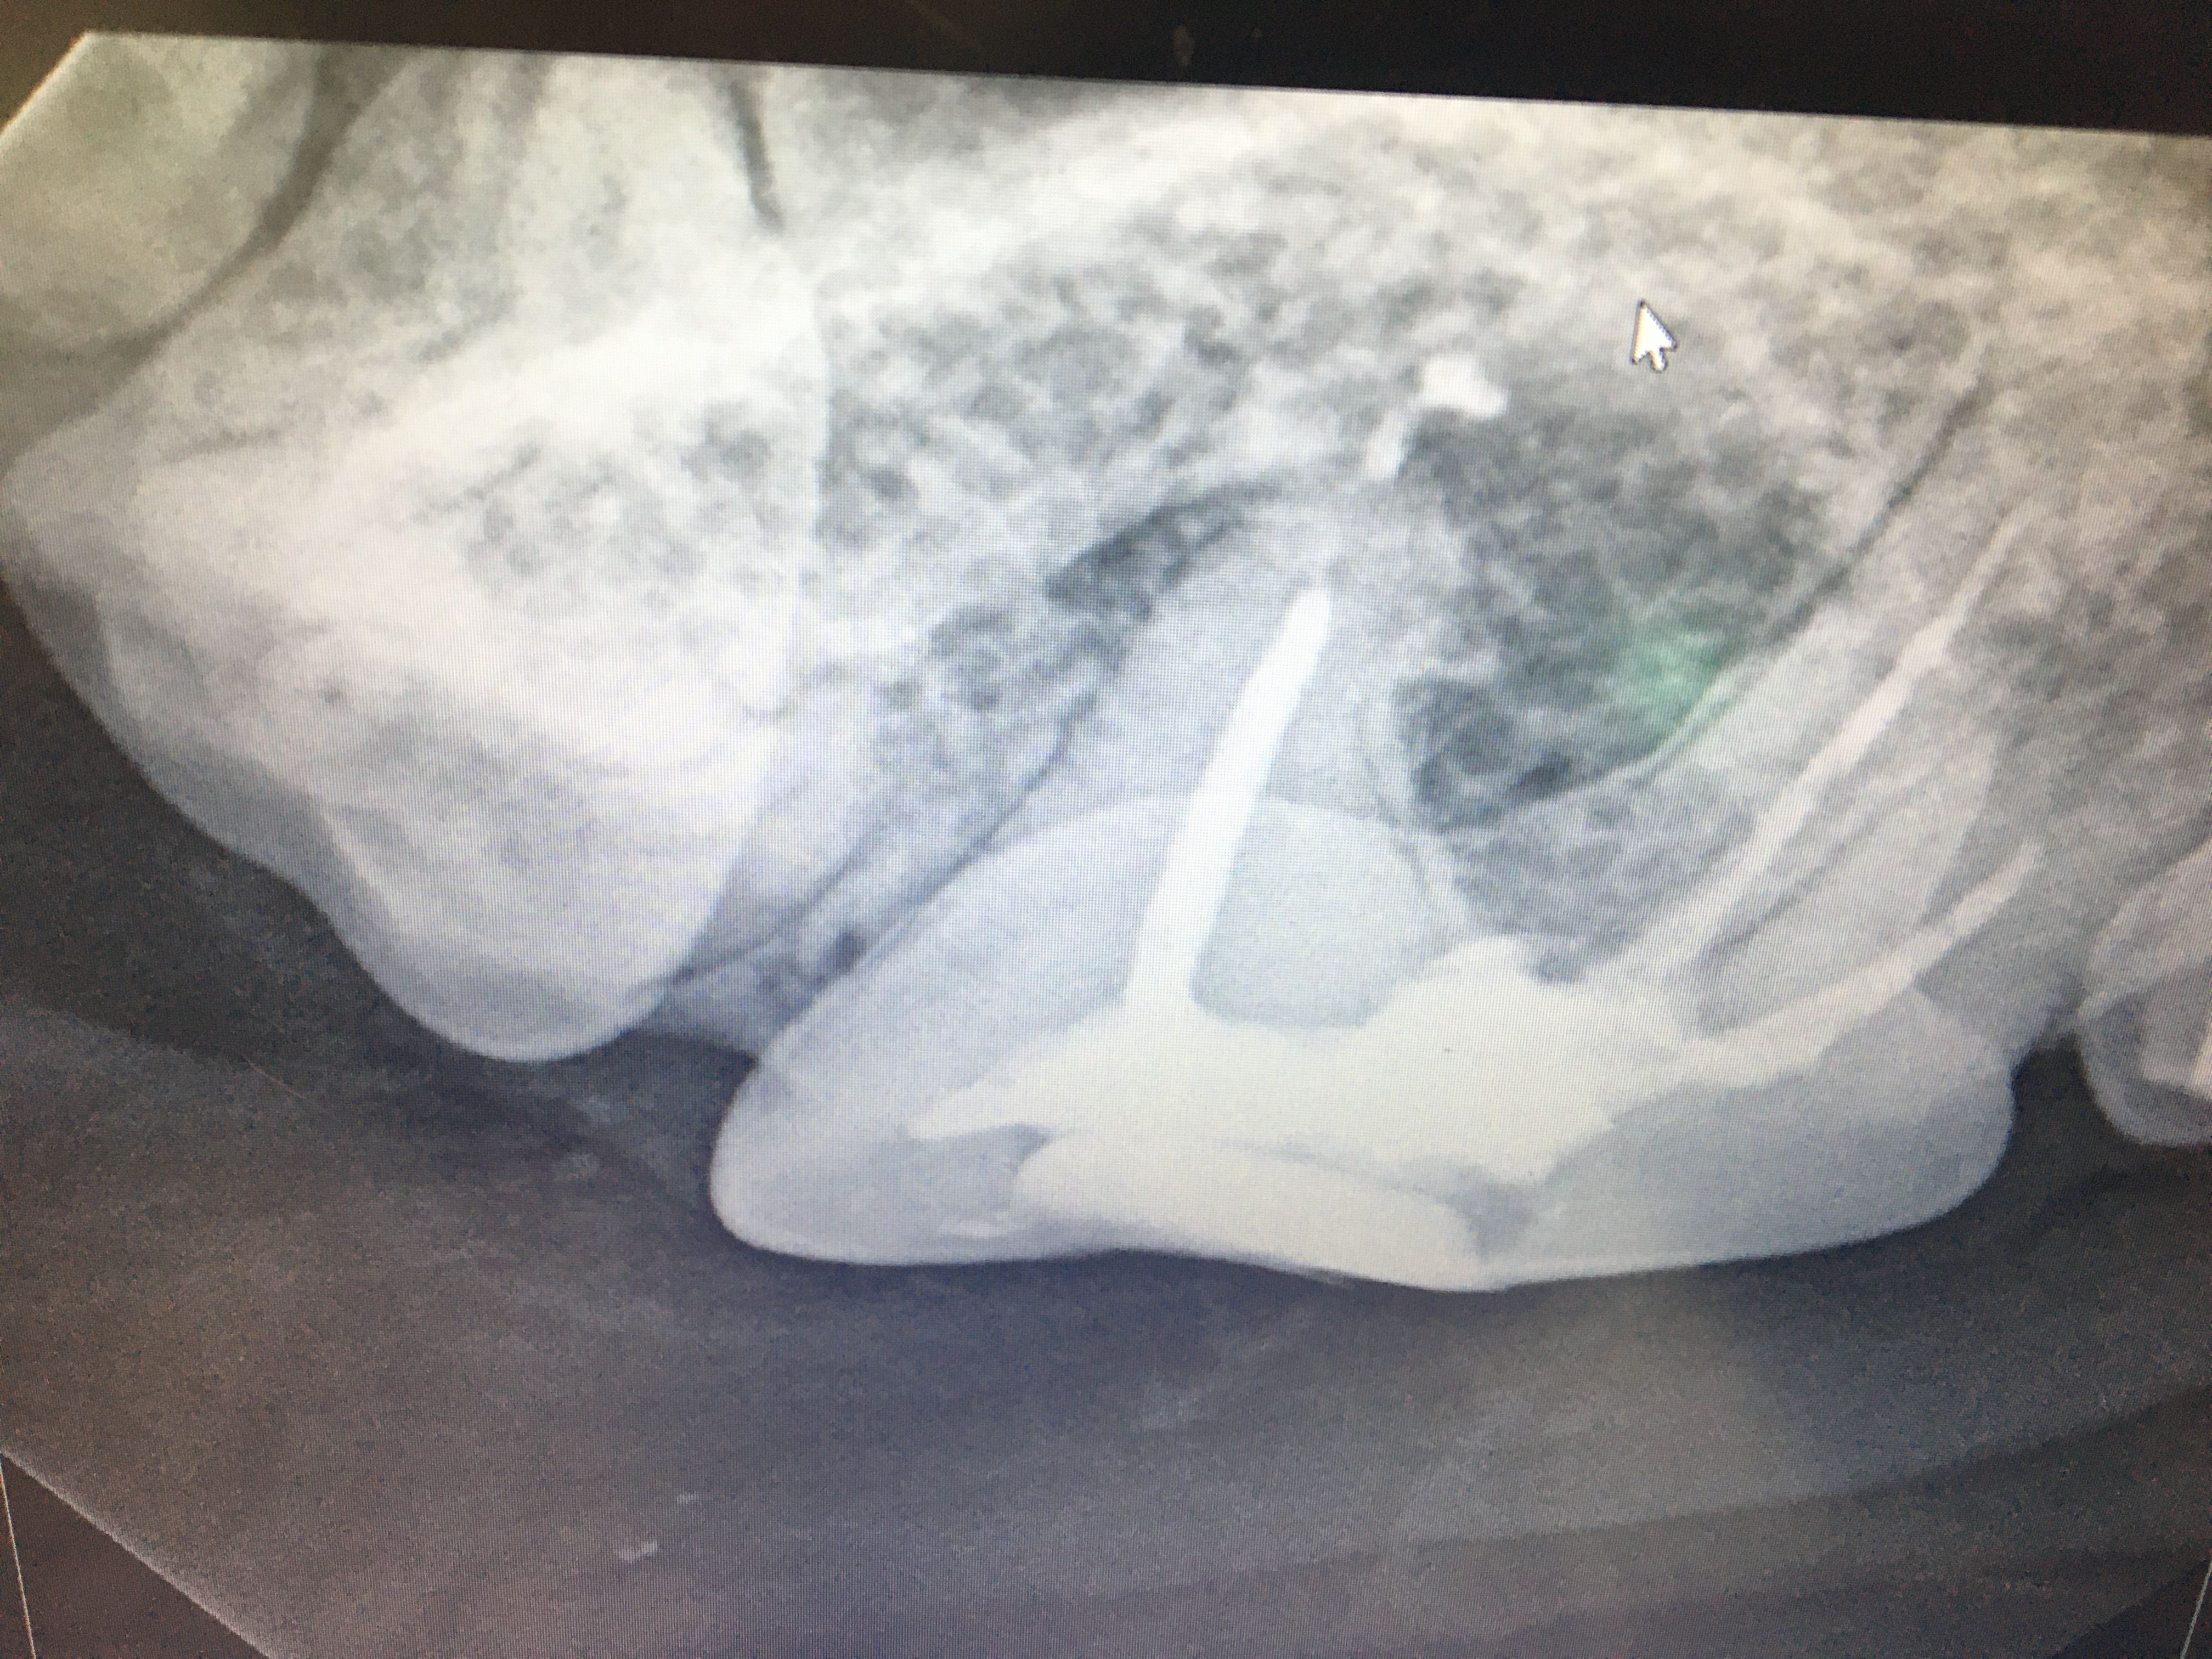

Radiography

Radiography is absolutely mandatory to perform effective dental or oral surgical treatment. In many zoos, sophisticated radiography equipment and techniques may not be available. That was certainly the case for many years at Milwaukee County Zoo. I found portable radiography units to borrow for early cases. I used rapid developer and fixer in metal cans and used red light bulbs in small utility or bathrooms to develop intraoral dental films.

We learned to use the zoo hospital table radiography unit with fine grain and mammography film for full head views that are fully adequate for dental treatment. Right and left obliques are taken at 45 degrees with the mouth open. With proper positioning, each film will isolate one mandibular arch and one maxillary arch. Then with maxillary and mandibular dorsal-ventral intra orals, one will be provided with complete views of the entire arch.

When I installed digital radiography in my dental practice we used our conventional dental film automatic developer at the zoo hospital for intraoral films.

We are now fortunate to have a Nomad portable unit and digital radiography capacity at MCZ for dental cases. This technology certainly improves our efficiency for treatment.

In personal conversations with Dr. Thomas Clark at Louisville Zoo I learned that he also has had success with silver amalgam. The lesion must be prepared with inverted cone burs to establish mechanical retention. These restorations have held up without failure for many years, see photos.